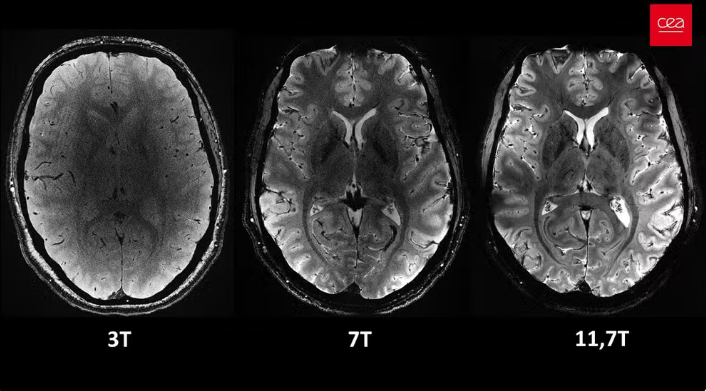

O campo magnético criado pelo scanner é de 11,7 teslas. Essa potência permite que a máquina escaneie imagens 10 vezes mais precisas do que os aparelhos normalmente utilizados em hospitais – cuja potência geralmente não supera os três teslas.

Em uma tela de computador, Vignaud comparou imagens tiradas por esse poderoso scanner, apelidado de Iseult, com imagens de uma ressonância magnética normal.

“Com essa máquina podemos ver os pequenos vasos que alimentam o córtex cerebral, ou detalhes do cérebro que eram quase invisíveis até agora”, detalha.